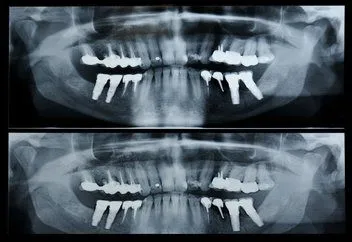

Panorex

Pan_x_ray.jpg This unique panographic x-ray is a valuable tool that has many applications:

1.  Fractures of the teeth and/or jaws can be seen when it is difficult to open the mouth.

2.  Viewing development, position, and eruption of primary teeth so we can see all of a child’s baby teeth and permanent teeth at one time

3.  For individuals who have difficulty holding x-ray films in their mouth

4.  Diagnosing temporomandibular joint (jaw hinge) dysfunction

5.  Viewing impacted wisdom teeth

6.  Detecting presence of bone or gum diseases

7.  Diagnosing early signs of oral cancer

8.  Discovering nonmalignant tumors

9.  Surveying the sinus region

10. Discovering stones in the salivary glands

11. Examining trauma patients

12. Screening for stroke, osteitis deformans, hyperparathyroidism and other systemic diseases

13. Obtaining baseline data for long term dental health

14. Diagnostic data for a referring dentist to use

15. Critical for setting broken facial bones

16. Identification in case of an accident

17. Provide signs of carotid calcification. Alveolar bone loss is sometimes associated with cardiovascular diseases.

18. Evaluation for full or partial removable dentures, dental implants, or braces.

19. New patients to help screen for diseases beyond just the teeth.

20. Screening for osteoporosis

21. Metastases.  Carcinomas of the breast, lung, prostate, thyroid gland, kidney, and colon may produce cyst-like growth in the jaw.

22. Genetic abnormalities

23. Developmental abnormalities like cleft palate

24. Asymmetry of the oral and maxillofacial area which could be caused by swelling on one side of the face as seen in eating disorders.

25. Altered nerve sensation-paresthesia in lip,  or hypersensitivity which could be caused by infectious osteomyelitis or  a malignancy compressing a nerve

26.  Finding the cause and location of pain

27.  Ill-fitting dentures due to alveolar bone loss